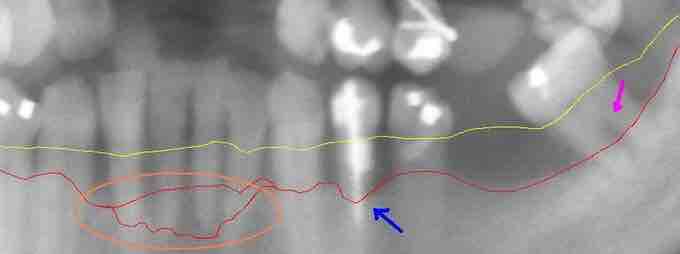

Extensive periodontal disease

This section from a panoramic x-ray film depicts the teeth of the lower left quadrant, exhibiting generalized severe bone loss of 30–80%. The red line depicts the existing bone level, and the yellow line depicts where the gingiva was originally (1–2 mm above the bone), prior to the patient developing periodontal disease. The pink arrow, on the right, points to a furcation involvement, or the loss of enough bone to reveal the location at which the individual roots of a molar begin to branch from the single root trunk; this is a sign of advanced periodontal disease.